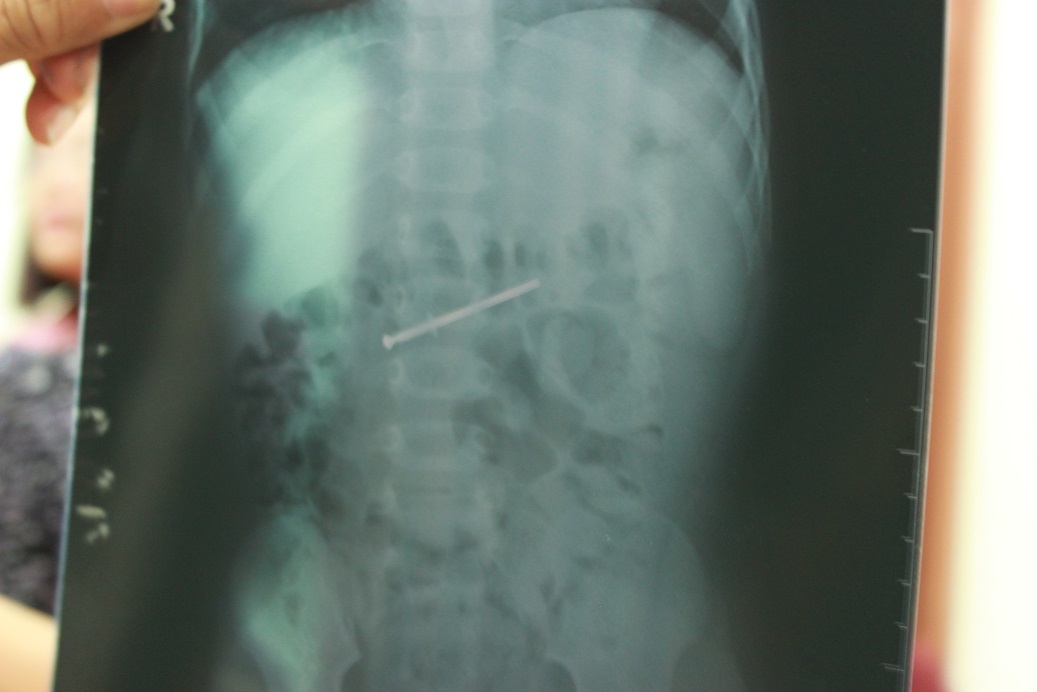

"Sau khi chụp phim X-quang, chúng tôi phát hiện dị vật trong ruột non của bé và tiến hành nội soi. Cây đinh di chuyển nên đã làm tổn thương và trầy xước dạ dày của bé. Rất may mọi chuyện chưa diễn tiến quá phức tạp", bác sĩ Dũng cho biết.

Cây đinh qua phim chụp X - Quang |